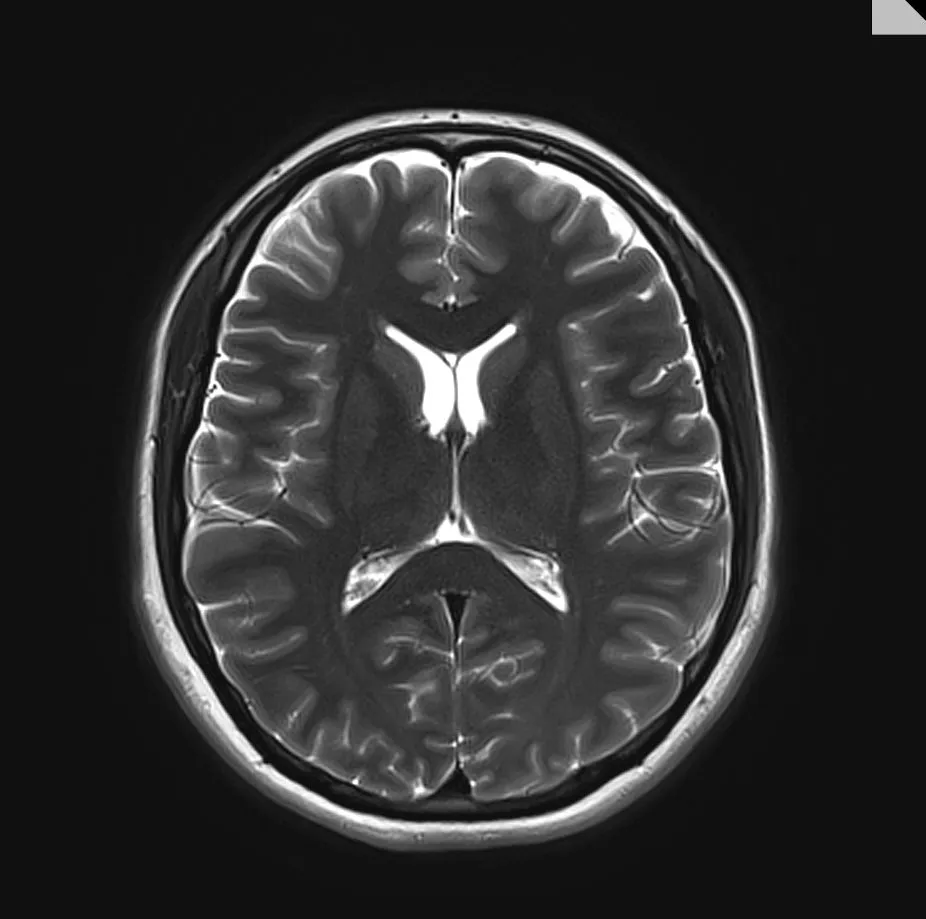

The team of 20, from the Universities of Edinburgh and Dundee, has approval to use a large data set made up of CT and MRI brain scans from patients in Scotland from 2008 to 2018, representing 1.6 million images.

The team will use artificial intelligence and machine learning to analyse the image data alongside linked health records such as demographics and treatment history, without patients being identifiable, to find patterns that could indicate a person’s risk of developing dementia.

The ultimate aim is to build a digital healthcare tool that radiologists can use when scanning for other conditions to determine a person’s dementia risk, and to diagnose early stages of related diseases, such as Alzheimer’s.